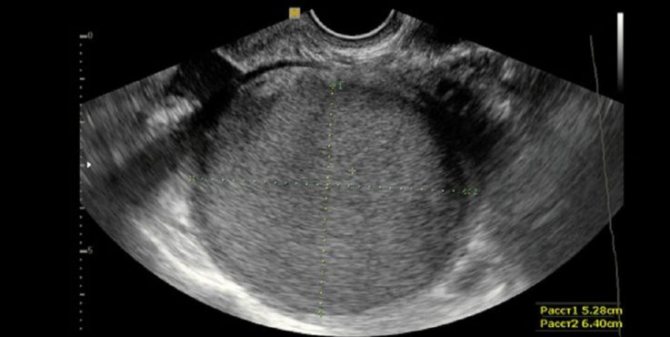

- УЗИ-исследование органов малого таза;